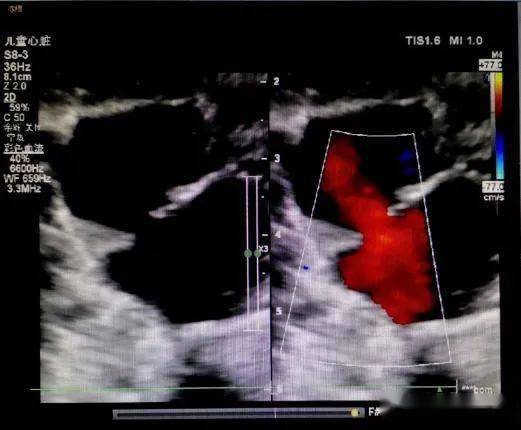

儿童超声心动图